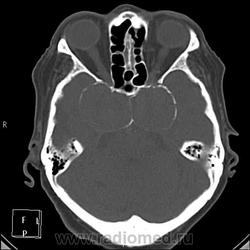

А контраст почему не делали? Больше похоже на тромбированные аневризмы

Неужели такие аневризмы? Бывает же! А сканы с контрастом есть?

Да простят моё нахальство уважаемые специалисты КТ. Я вижу тут огромные инкапсулированные узлы расположенные почти симметрично справа и слева от турецкого седла, которое разрушено узлом поменьше. Латеральные злы продавливают дно средней черепной ямы. По-видимому, здесь доброкачественная опухоль типа «аденома», исходящая из гипофиза и давно растущая. Обызвествление есть не только в капсулах узлов, но и в их толще (очаговое). При таких размерах узлов и косных разрушениях, нет сомнения, пострадали и зрительные нервы.

Цифровых и плёночных доказательств на руках нет. Опухоль диагностирована в 2004 году, размером "с вишню", дебютировала птозом века правого глаза, умеренной головной болью в лобной области слева и постепенным снижением зрения, катаракта. Пациентка с трезвом уме и превосходной памяти (на мой субъективный взгляд))). В выписке результаты КТ, МРТ: неоперабельная опухоль селлярно-параселлярной области с прорастанием кавернозных синусов, аневризма сифона внутренних сонных артерий. Цитологию НЕ брали.

По поводу изменений правой височной области: и дочь, и сама пациентка отрицают в анамнезе инсульт.

И то, и другое. Доказать без контрастирования не могу. Когда сама впервые увидела, анамнеза не знала, подумала о двусторонней аневризме. И не угадала.

Насчет опухоли у меня большие сомнения. То что седло растянуто, еще не показатель. Седло увеличивается в размерах даже при гипертонии,а тут такие аневризмы. Самой опухоли не видно, в просвете турецкого седла медиальные полюса аневризм. Ну впрочем не так это важно, интерес чисто теоретический, да и верификации видимо не будет. Спасибо большое за демонстрацию.